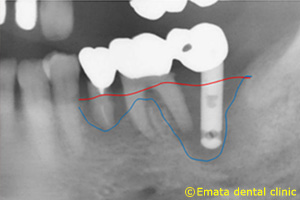

インプラント周囲炎の治療例

インプラント治療

インプラント周囲炎2